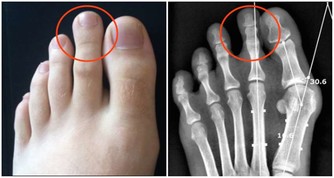

而當血脂積累過多就會沉積在血管壁上,並逐步形成動脈粥樣硬化斑塊,造成血管變得狹窄,從而導致心腦血管疾病風險蹭蹭漲~